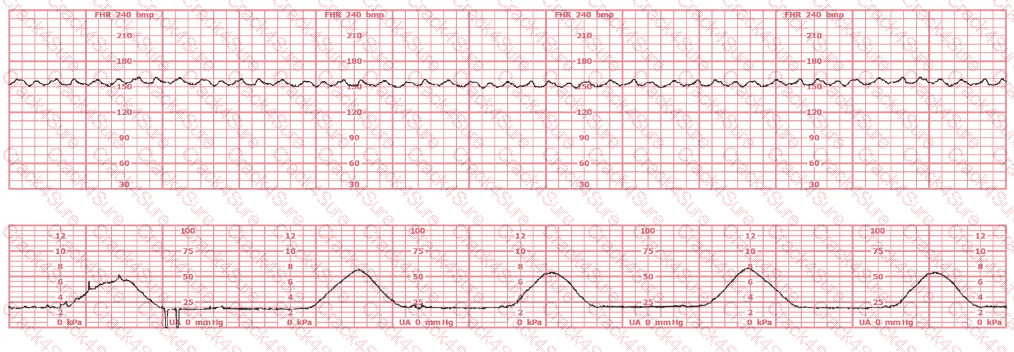

A woman in labor has been pushing for 4 hours. For the last 2 hours, there have been recurrent variable decelerations. Variability has evolved from moderate to minimal. Cervical exam is 10/100%/+2, fetal head OP. There has been no fetal descent for the last 45 minutes. Based on the tracing shown, the most reasonable approach is